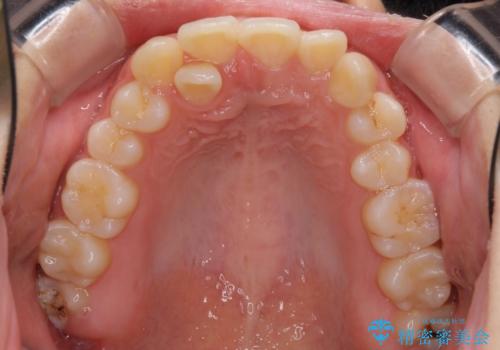

インビザラインが続けられない ワイヤー矯正での抜歯矯正 その2

- 八重歯やデコボコをインビザラインで治療したいとのことで来院された患者様です。

インビザライン単体で治療を行うには叢生が強いと判断されたため、事前にワイヤー装置で抜歯矯正を行い、ある程度改善してからインビザラインにて仕上げていくこととしました。